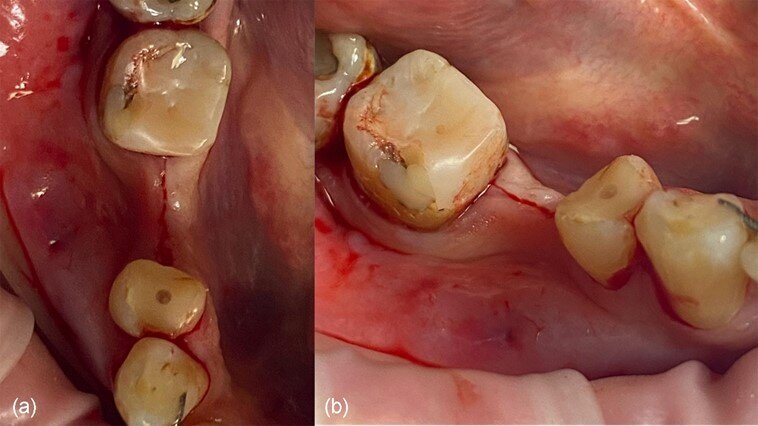

Una paziente di 51 anni di sesso femminile ha frequentato la nostra clinica cercando una riabilitazione in un sito edentulo inferiore 46. L’elemento dentale 46 è stato estratto più di 4 mesi prima della consulenza e non è stato utilizzato alcun materiale per la conservazione dell’alveolo. La paziente era una non fumatrice in buona salute, senza malattie parodontali (nessuna perdita di attacco, tasche al sondaggio e BoP). È stato eseguito un esame pre-operatorio con tomografia computerizzata a fascio conico (CBCT) nel quarto quadrante inferiore, che ha rivelato una significativa perdita ossea orizzontale nella zona edentula (Fig. 1). La densità ossea è stata classificata come tipo 2 e la distanza dal margine alveolare più coronale al canale alveolare inferiore era sufficiente per posizionare un impianto dentale (più di 10 mm) (Fig. 1). L’esame clinico ha rivelato una larghezza del tessuto cheratinizzato di più di 4 mm sulla cresta comunque sottile (Fig. 2). Il paziente è stato trattato con la tecnica del Poncho Lamina per un processo di ottimizzazione in un solo passo (Processo O.S.O.) nel sito 46. In questo caso, abbiamo selezionato e utilizzato un impianto MIS V3 (MIS Implants Technologies) e una ben documentata barriera corticale Soft Lamina 25x25 (Osteobiol by Tecnoss). L’ottimizzazione del tessuto molle è stata ottenuta con un moncone personalizzato generato tramite il sistema VPI Cervico (VP Innovato Holdings).

Fig. 2_Situazione iniziale del sito 46: a) vista occlusale, b) vista vestibolare.